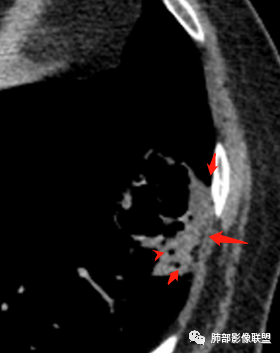

病灶分两部分

周围大片GGO

中央囊实性病变

囊腔有张力,外形有分叶,壁厚薄不均,有间隔,有强化

影像特点:

1、左肺下叶外基底段不规则囊腔样病灶,囊腔内有条形影及血管穿行。

2、囊壁薄厚不均匀,稍显僵硬,有壁结节(对应边缘分叶等)、结节强化明显。

以上两条几乎将肺囊肿彻底排除在外,且高度怀疑新生物!